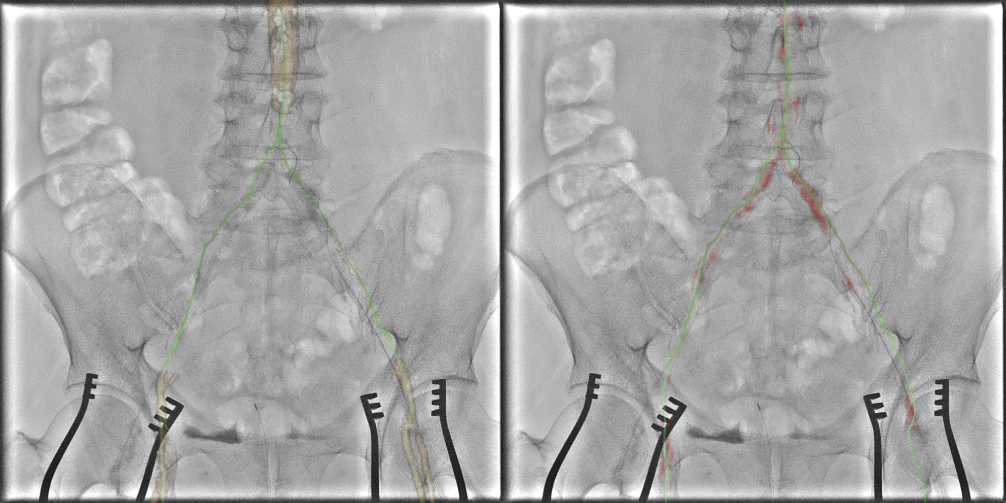

下肢血管における使用例を示す。術前CTAではAortic bifurcationからの完全閉塞となっていた(図5)。完全閉塞部分へのアプローチに対して難渋することが予測されたため、下肢血管解析結果を用いた3D Roadmap使用を検討した。AWVS7は下肢血管解析ソフトを用いることで自動的に血管、骨(術中3D Roadmapの位置合わせ用)を作成する(図6)。狭窄症例などでは自動作成された血管3Dを透視と重ねる3D Roadmapが治療サポートになるが、CTO症例ではワイヤーを進めるためのラインの有用性に着目し、CTO部分を含めた血管センターラインを作成した(図7)。血管センターラインはワイヤーを進める際のReferenceとして有用(図8)であり、3次元での位置情報を有したラインであるため、角度変更やFOV変更、テーブル移動にも追従する。また治療前のDSAでは表示されないTrue面を表示させることは、手技を進めていく中で有用なサポートになったと当院医師よりフィードバックがあった。3D Roadmapは術中にボリュームレンダリングの透過度変更や表示の有無、センターラインの表示の有無も変更可能である。CTO部分を通過させている場合にはセンターラインの表示、通過後のバルーン拡張やステント留置時にセンターラインではなく、ボリュームレンダリング表示による病変部の逆描出など場面に合わせた変更を可能としている。また任意5倍までのデジタルズーム表示機能もあり、今後の症例で使っていきたい。

IGS740_SendaiTokusyukai_08.jpg図8 術中での3D Roadmap(左図は血管Volume、右図は石灰化Volumeをfusion)

完全閉塞部分を含めた血管センターライン:緑色